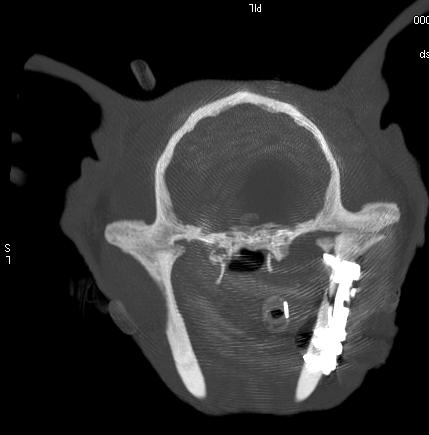

Both post op CT scans – Axial image from a post-operative CT scan showing excellent reduction of the fracture